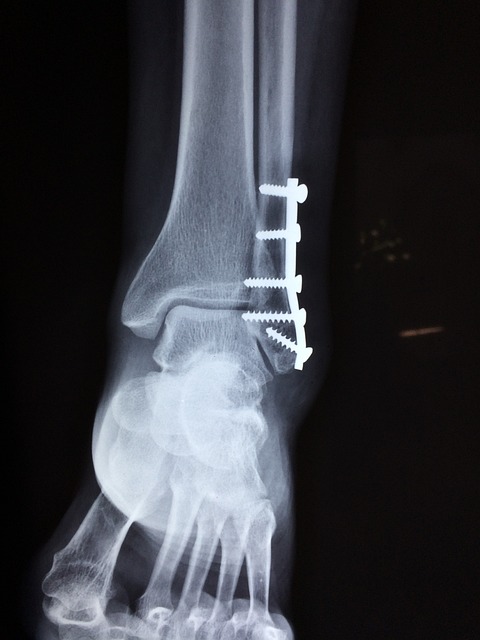

Sinds meer als vier weken ben ik geveld door een vervelende enkelbreuk. Ineens heeft het leven een compleet ander ritme. Voor de meest basale dingen ben je afhankelijk van je partner die ineens twee keer zo hard moet lopen. Een oneerlijke verdeling, maar wat doe je eraan? Laten we het erop houden dat het noodlot niet alleen bij mij heeft toegeslagen.

Ik geloof dat ik tot pechvogel van de zomer wordt gekroond. Een stapje gemist en dat resulteerde meteen in een enkel uit de kom plus een ingewikkelde breuk. Miljoenen mensen missen een stapje en er gebeurt niets. Het is zo’n beetje als de staatsloterij winnen maar dan in negatieve zin. Ineens wordt je confronteert met een ander zorgsysteem. In mijn geval beland je in een Italiaans ziekenhuis waar behalve de artsen niemand een woord buiten de deur spreekt. Het zorgt ervoor dat je je vrij eenzaam voelt maar de kundigheid van de verpleging is er niet minder om.

Het herstel van mijn enkel duurt lang en iedere dag die ik kan afstrepen is er eentje. Dankzij mijn fysio durf ik iedere dag een paar stapjes meer te doen. De angst om een verkeerde stap te zetten zit er diep in. De bedoeling is de enkel te belasten tot ik pijn voel maar de angst voor een misstap overheerst. Heel langzaam weet mijn fysio deze vrees weg te nemen. Hij had ook goed geld kunnen verdienen als psycholoog. Braaf kruip ik nu iedere dag op de hometrainer met de ijzeren wil het iedere dag een beetje langer vol te houden. Niet met de rolstoel naar de wc maar de krukken gebruiken. En zowaar gaat het leren lopen langzaam maar zeker telkens een beetje beter.